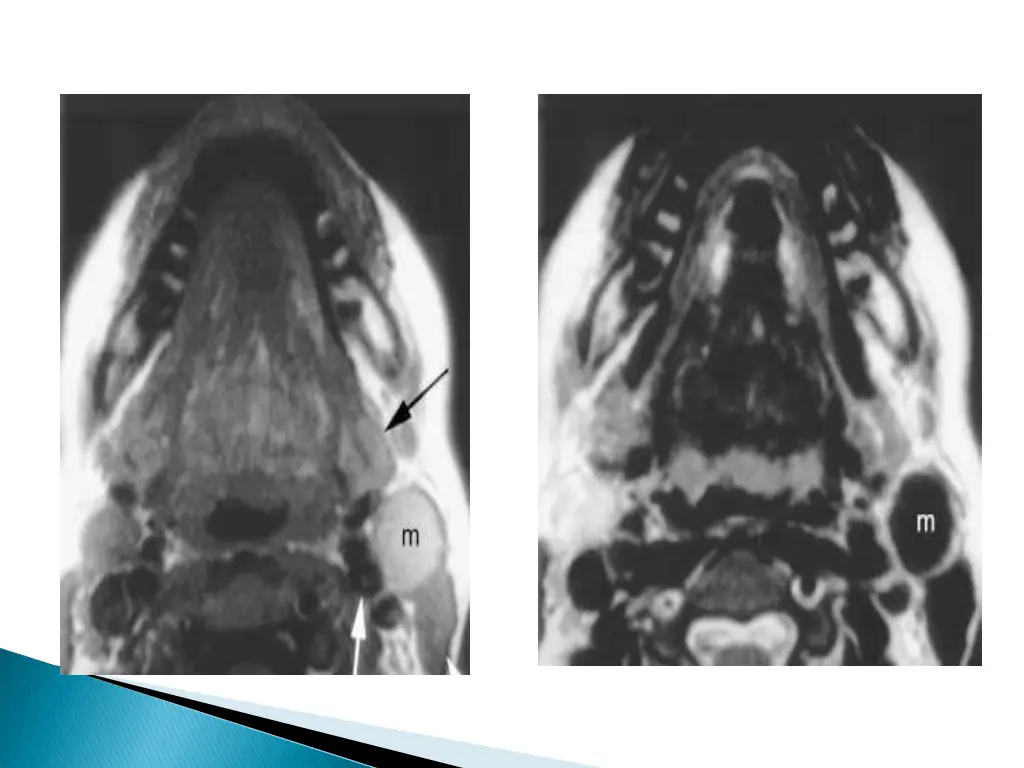

CHARACTERISTIC LOCATION : Along the anterior border of the SCM lateral to the carotid space and posterior to the submandibular gland. Displaces the carotid vessels : medially\ SCM : posteriorly or posterolaterally Submandibular gland : anteriorly May extend into the parapharyngeal space after extending through the stylomandibular tunnel and middle constrictor muscle.

MRI better depicts the deep tissue extent. Cyst fluid hypo/hyper on T1W and hyperintense on T2WI. Occasionally, BEAK SIGN : on axial CT/MRI image : pathognomic of a 2ndbranchial cleft cyst especially bailey s type III cyst It represents a curved rim of tissue or a beak pointing medially between the ECA and ICA.